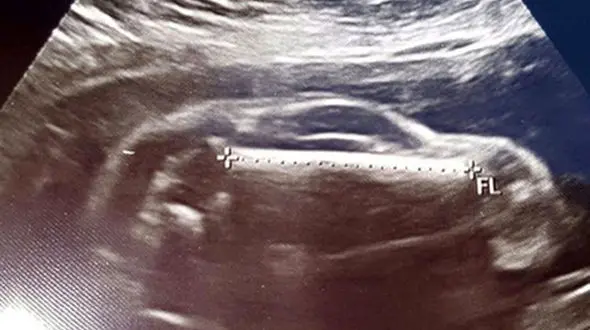

رکنا:ماجرای دیده شدن یک ماشین اسپرت در شکم زن حامله خیلی عجیب است.